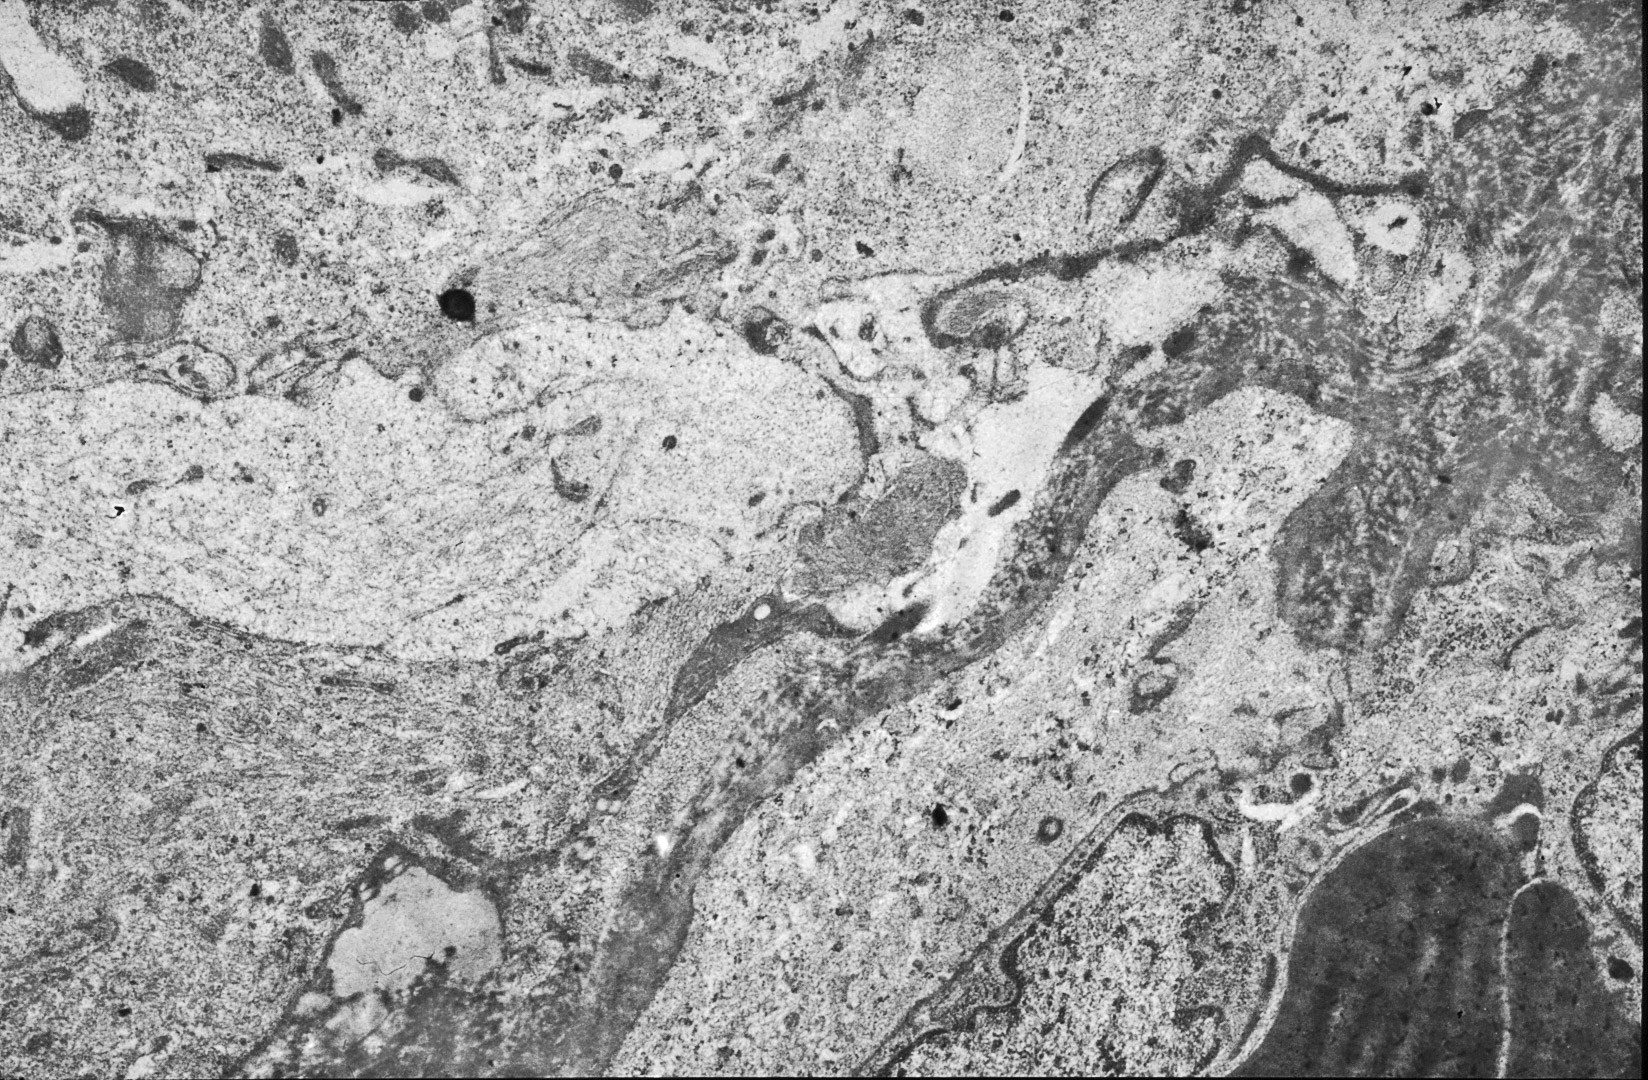

La popolazione cellulare è iperdensa,mostra un indice di coesione molto variabile con rare strutture giunzionali;la morfologia ultrastrutturale degli elementi è pleomorfa, condizione aggravata dai subentranti e progressivi processi regressivi e destrutturanti.

Sono presenti elementi fusati,ovoidali,poligonali di diverse volumetrie;come dato costante,si riscontra un nucleo voluminoso,irregolare,con cromatina addensata alla periferia e una quota citoplasmatica abitualmente esigua. La composizione del citoplasma di queste cellule appare variabile sia per squilibri quantitativi dei vari organelli, sia per i subentranti processi regressivi.

Anche il reticolo endoplasmico mostra segni ultrastrutturali di stress sia in associazione all’ergastoplasma sia in situazioni univoche.

Infatti,si repertano cellule di gliosarcoma con l’ ampio citoplasma occupato quasi interamente da queste formazioni; esse sono molto numerose, si trovano tra loro adese e mostrano le loro cisterne ectasiche o micro cistiche, creando così in una visione panoramica una immagine di aspetto cribroso .Lo spazio interno alle cisterne è apparentemente privo di contenuto, o, più raramente, è occupato da materiale amorfo, debolmente elettropaco.

Nel citoplasma delle cellule di gliosarcoma esaminate sono stati riscontrati con frequenza focolai di autofagosomi e di autolisosomi; i primi si riconoscono quali corpi ovoidali o rotondeggianti i quali sono demarcati da una membrana a doppio contorno e contengono nel loro spazio cavo materiale granuloso,filamentoso ed amorfo; i secondi,gli autolisosomi, sono delimitati da una membrana a monostrato,spesso notevolmente ispessita per sovrapposizione di materiale amorfo;il loro contenuto è rappresentato da materiale biologico in varie fasi di degradazione.